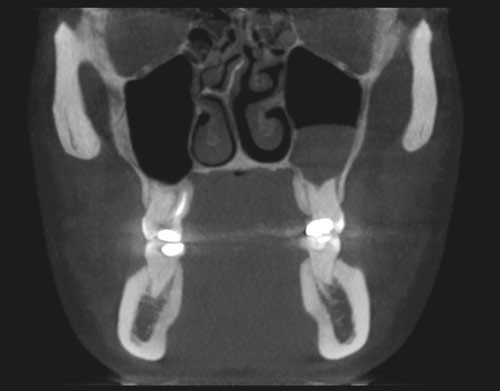

E-figur 3 og 4 viser CBCT-bilder av anatomiske strukturer i nese, maksille, strupehode og svelg. Det todimensjonale bildet viser retensjonspolypp i venstre maxillarsinus (e-fig 3), men det ble ikke funnet luftveispatologiske forandringer i strupehodet eller svelget (e-fig 4).